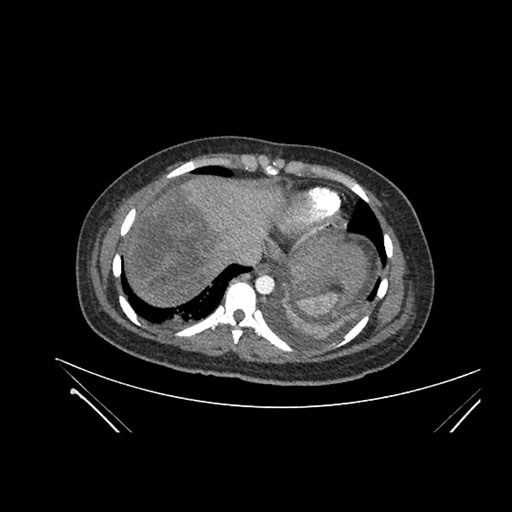

Axial Venous